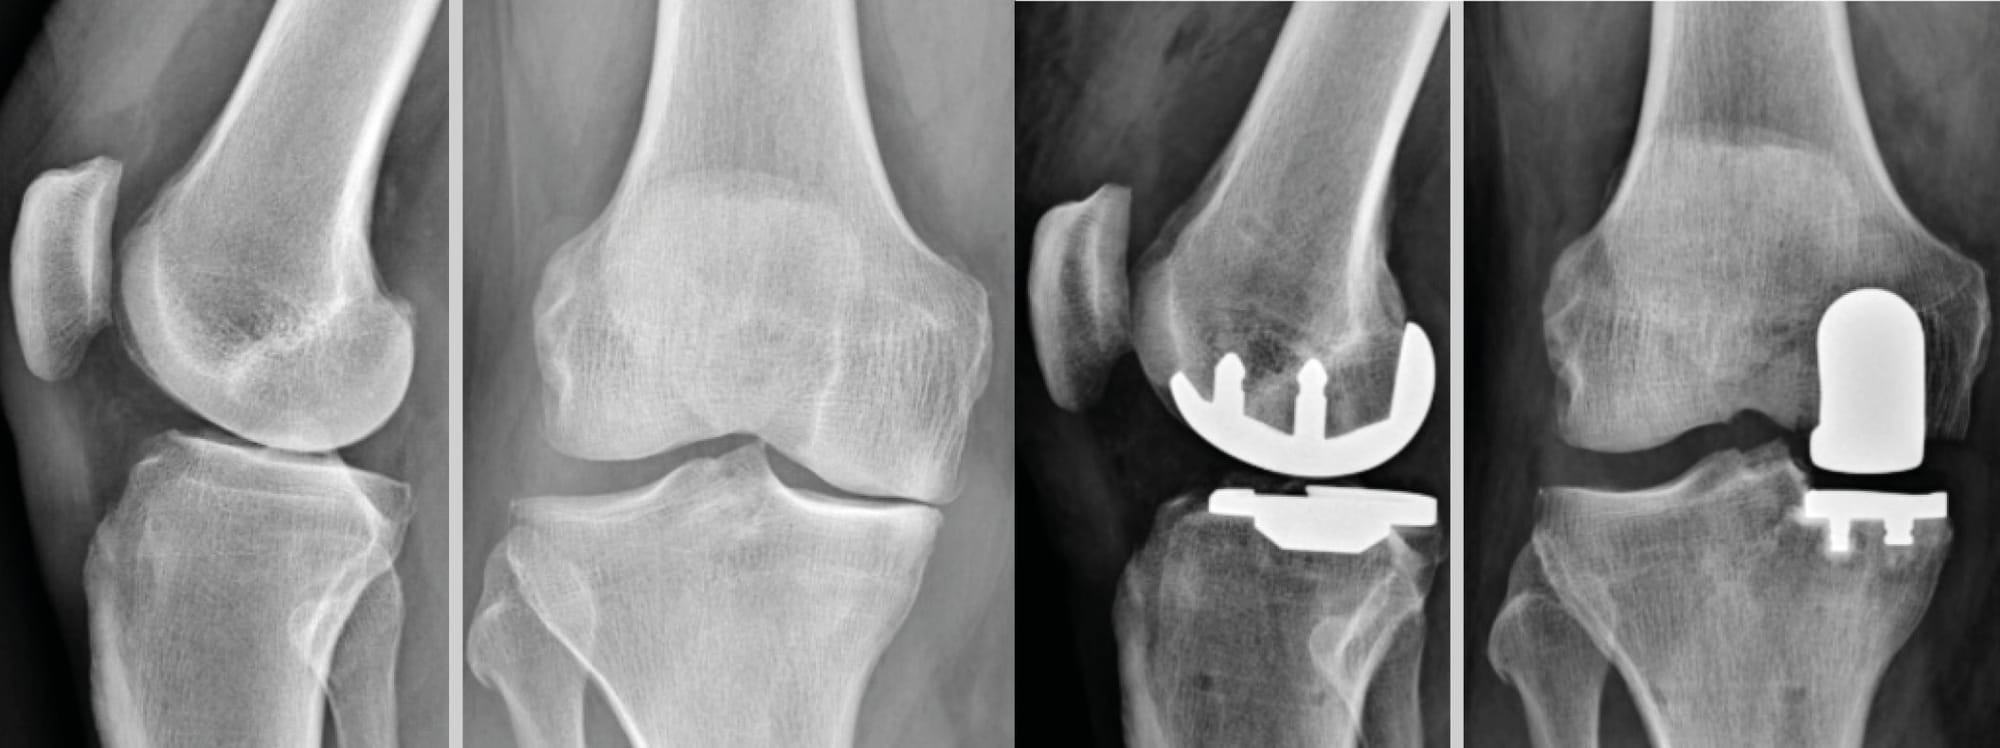

Our article focuses exclusively on unicompartmental knee arthroplasty (UKA), particularly the implantation of the Sigma™ Partial Knee prosthesis, a cemented, resurfacing-type prosthesis, suitable for the management of medial (Figure 1) or lateral (Figure 2) femorotibial osteoarthritis.